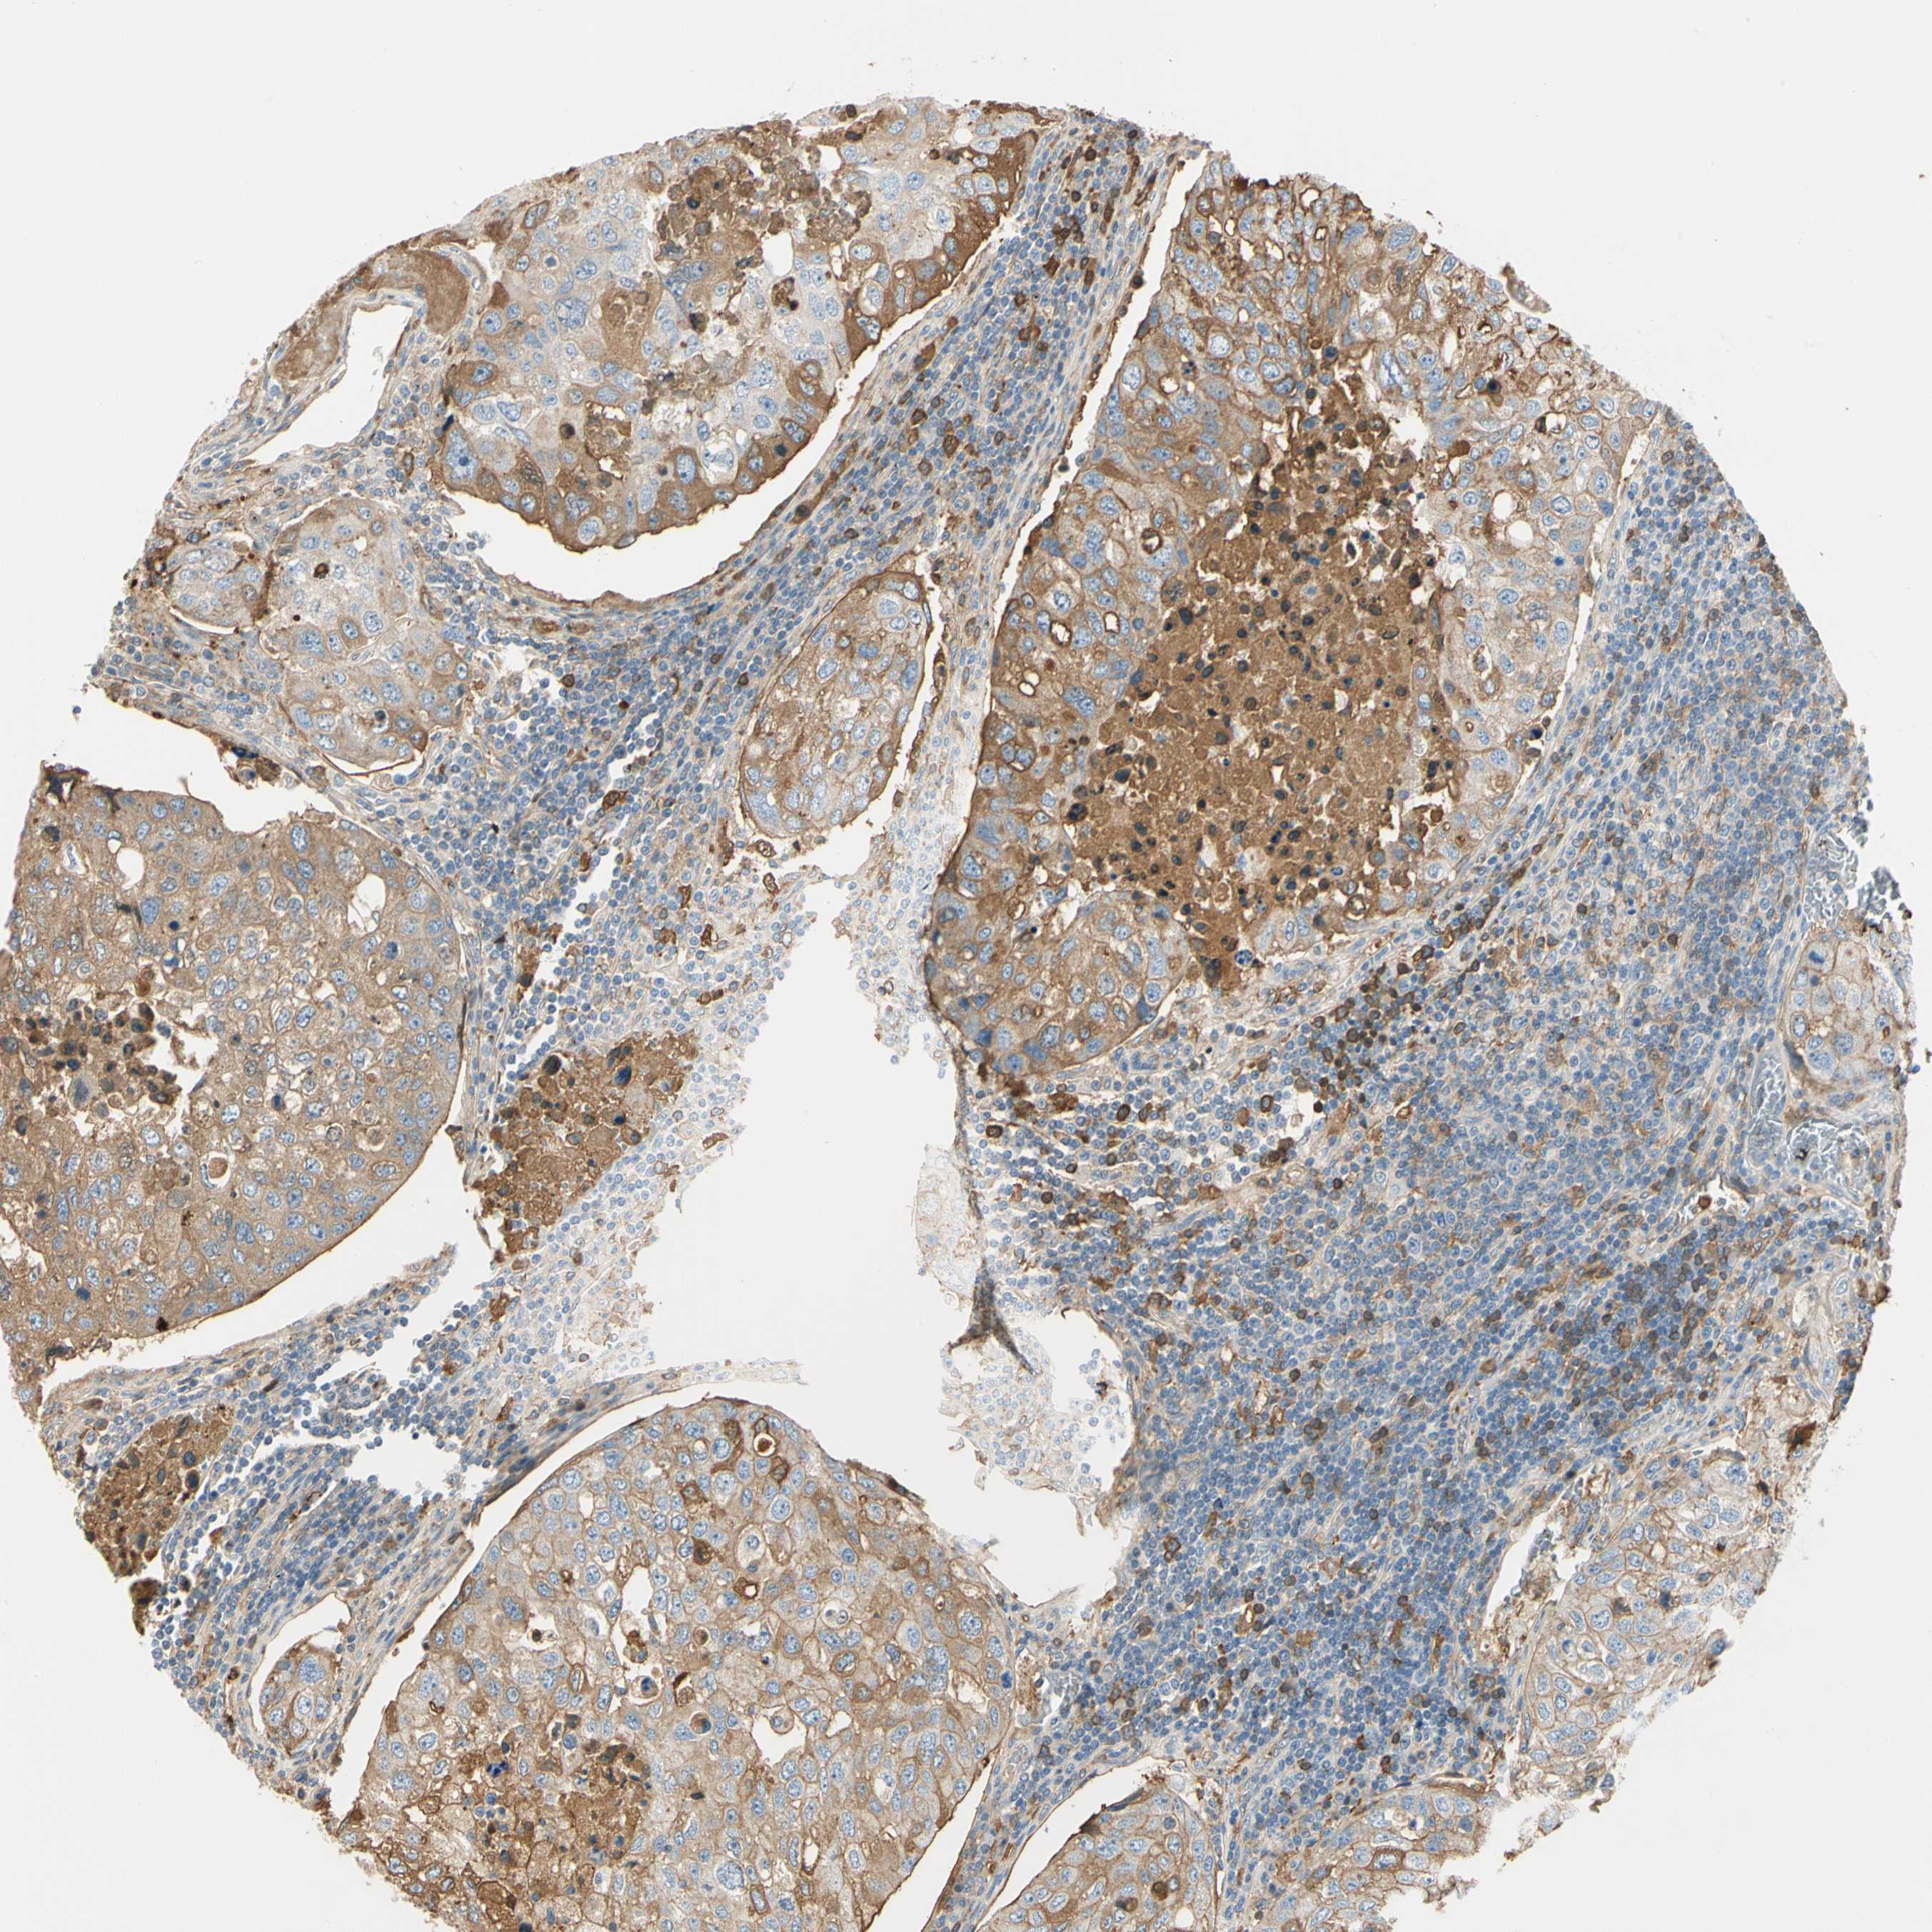

UROTHELIAL CANCER - Protein expressioni

A mouse-over function shows sample information and annotation data. Click on an image to view it in a full screen mode. Samples can be filtered based on level of antibody staining by selecting one or several of the following categories: high, medium, low and not detected. The assay and annotation is described here.

Note that samples used for immunohistochemistry by the Human Protein Atlas do not correspond to samples in the TCGA dataset.

Antibody stainingi

Antibody staining in the annotated cell types in the current human tissue is reported as not detected, low, medium, or high, based on conventional immunohistochemistry profiling in selected tissues. This score is based on the combination of the staining intensity and fraction of stained cells.

Each image is clickable and will lead to virtual microscopy that enables deeper exploration of all samples and also displays staining intensity scores, fraction scores and subcellular localization as well as patient and tissue information for each sample.

Antibody HPA008069

Antibody CAB078183

Staining

High

Medium

Low

Not detected

Intensity

Strong

Moderate

Weak

Negative

Quantity

>75%

75%-25%

<25%

None

Location

Nuclear

Cytoplasmic/membranous

Cytoplasmic/membranous,nuclear

Urothelial carcinoma, Low grade

Urothelial carcinoma, High grade

Urothelial carcinoma, NOS